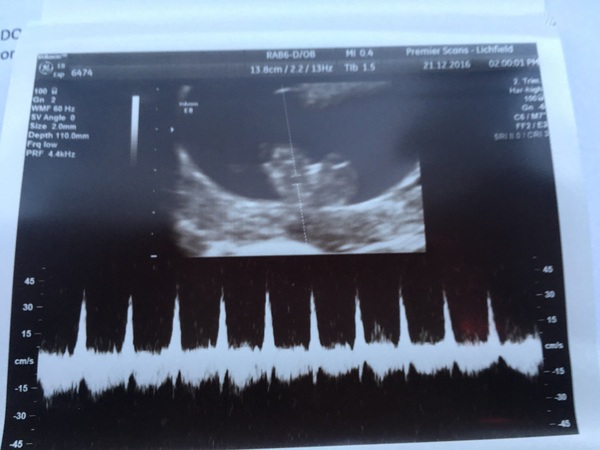

Thought I'd just share this with you lovely ladies. My dates are 8+6, measuring 9 so not bad. Saw and heard the heart beat. Was in tears all the way through, so happy. Finally feels real and like the nausea is worth it to see the little bean. It was even doing a little waggle dance inside which made me laugh!! Got some lovely pics too. This is our favourite as it shows the heart beat. Nice and strong. Just what we needed to see before Christmas!